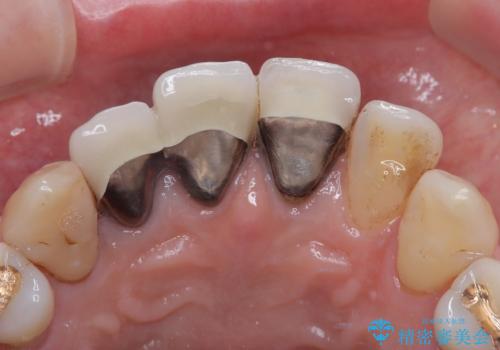

- 昔入れた前歯を綺麗にしたいことを主訴に来院された患者様です。

根尖に病変を認めたため、根管治療を行いセラミッククラウンにて修復を行なっています。

根管充填はMTAにて行なっています。